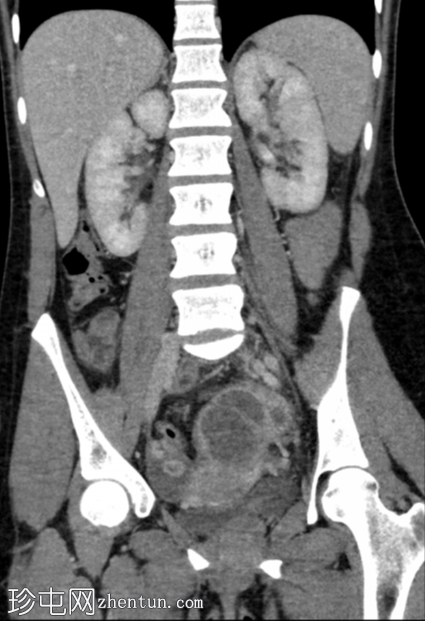

冠状位增强扫描(门静脉期)

左侧附件可见多房性管状、迂曲囊性病变,囊壁不规则增厚,内部可见碎屑和分隔,符合输卵管积脓的诊断。左侧卵巢未单独显示。

盆腔少量腹水,盆腔腹膜脂肪间隙轻度模糊。

右侧卵巢可见一小黄体囊肿,边缘增厚并有强化。

子宫周围静脉通道明显,提示轻度盆腔充血综合征。

典型的放射学特征如本例所示,包括管状多房性复杂附件病变,伴有碎屑、分隔和不规则的厚壁,这可以确诊为输卵管积脓。